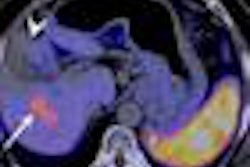

Nueclear Healthcare will offer PET/CT and SPECT scanning facilities through standalone centers, the companies said, colocating cyclotrons in cities with potentially high demand.